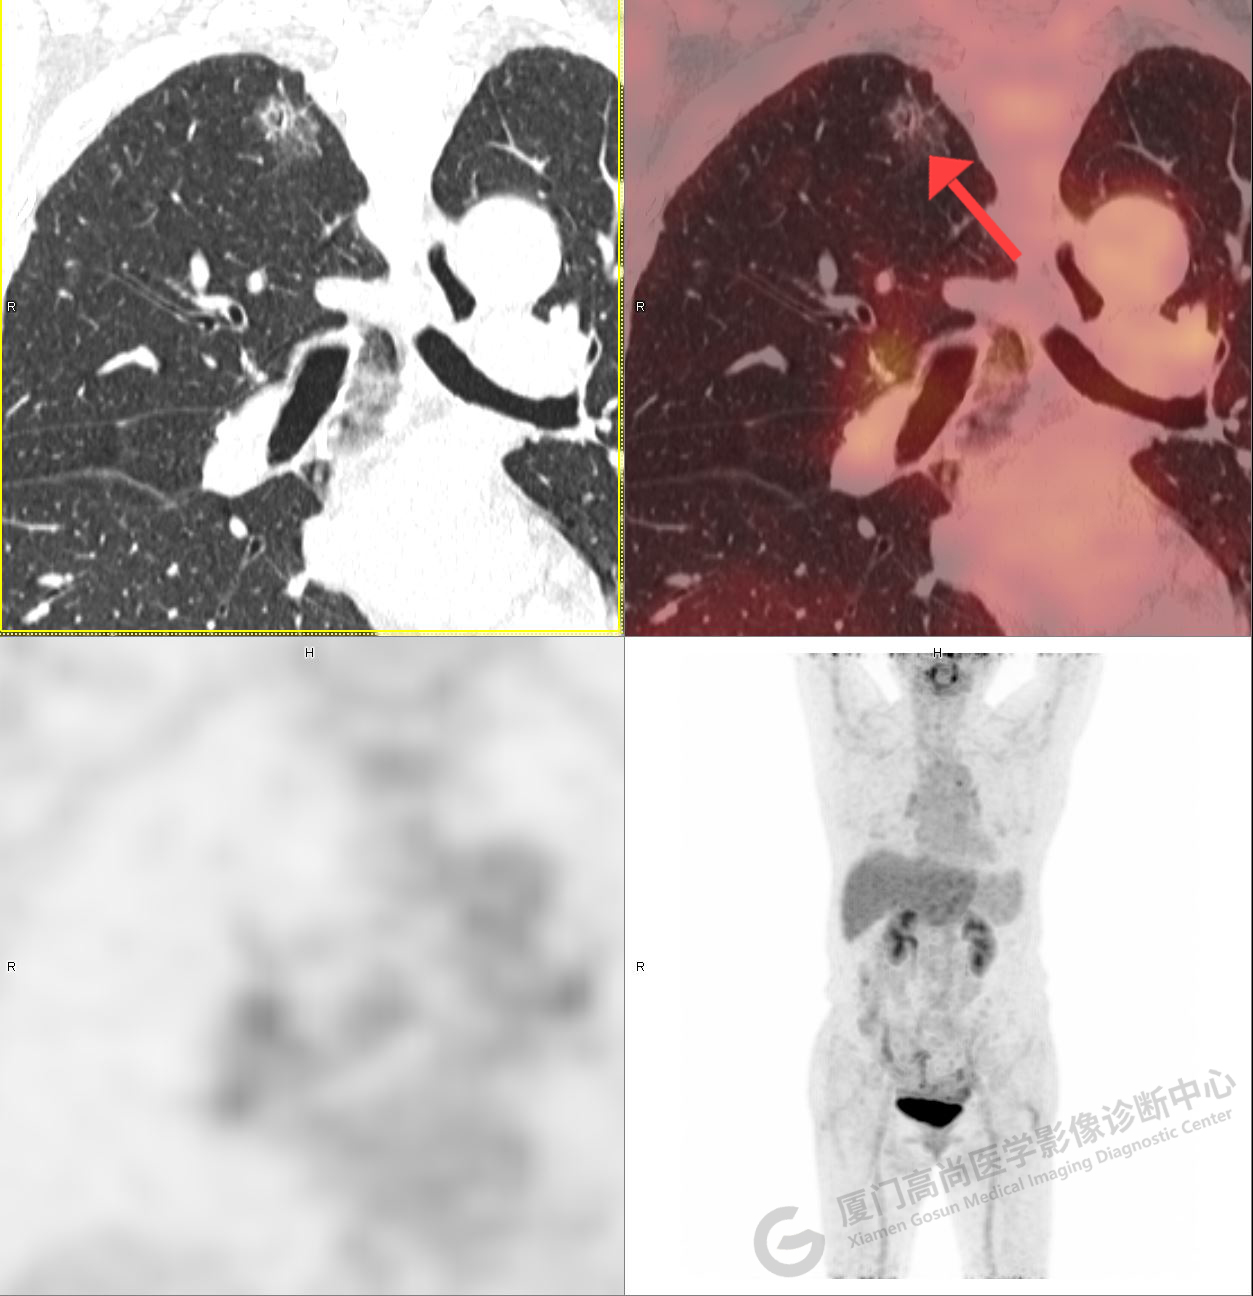

PET/CT影像圖

圖1

圖2

PET/CT示:右肺下葉結(jié)節(jié),代謝增高,考慮為周圍型肺癌,建議穿刺活檢。

病理證實(shí)是肺腺癌。